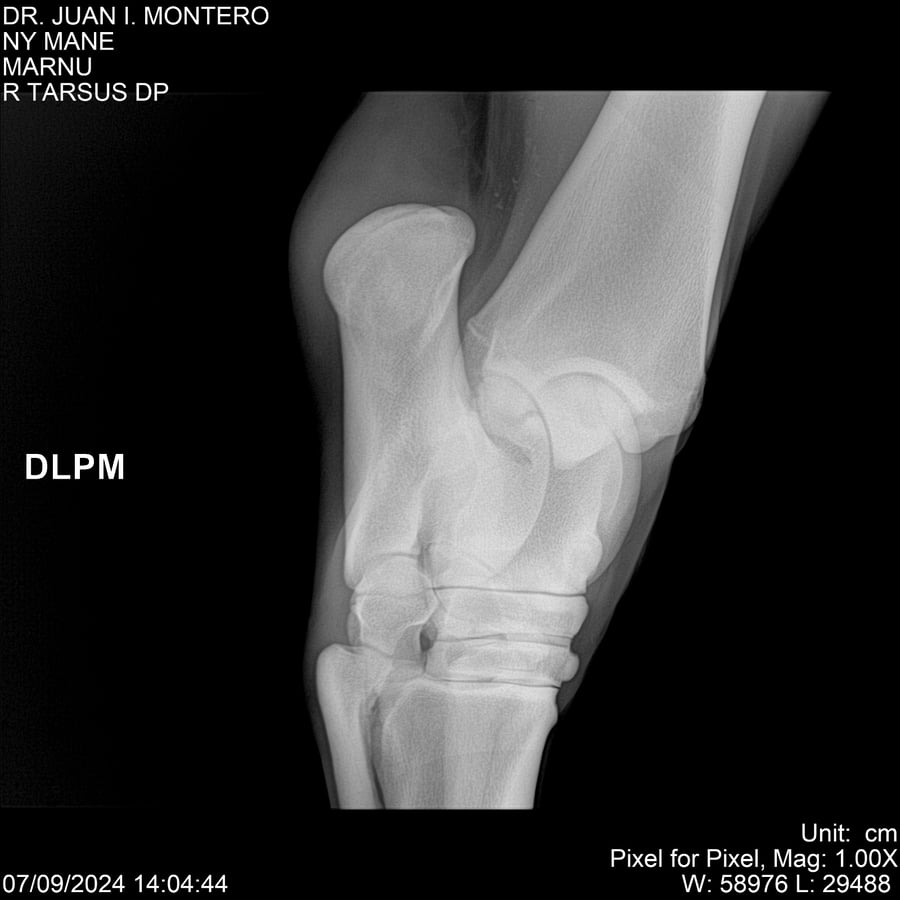

LOTE 20, NY MANE Lote Anterior Volver al remate Lote Siguiente Ficha Contacto Montevideo - Ficha del Lote Identificador: #282520 Categoría: Yeguarizos 76 Visualizaciones ClicData Contacto Empresa: Abelenda N. R., Walter Hugo Nombre*: Teléfono* : E-mail* : Mensaje Enviar Registrese gratis Este contenido Exclusivo está disponible sólo para usuarios registrados Ingresar